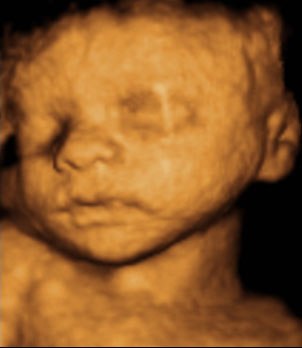

Kan da lige sætte et par billeder ind fra i mandags, hvor jeg var 27+5 uger henne, så du kan se kvaliteten

Vedhæftede fotos (klik for at se i fuld størrelse)